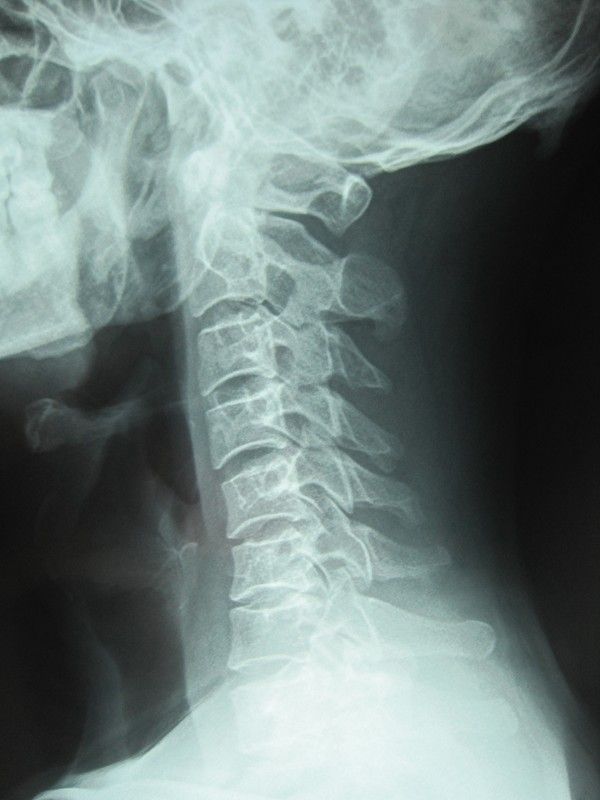

颈椎x片正常

颈椎x片正常,

谁能帮我看下这个x光片啊,颈椎不舒服,那个医生只给我做了个拔罐然后